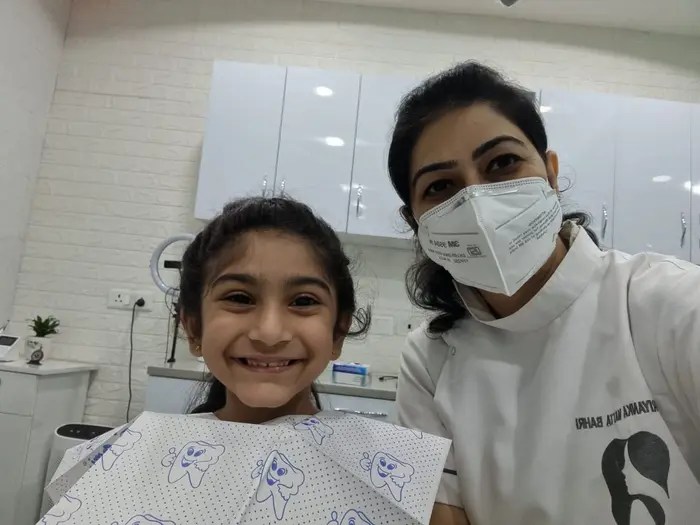

We are specially trained to work with children and can help ensure that their dental visits are comfortable and stress-free. We also provide education and resources for parents to help them promote good oral health habits at home. Overall, kids dentistry plays an essential role in promoting the oral health and well-being of children.